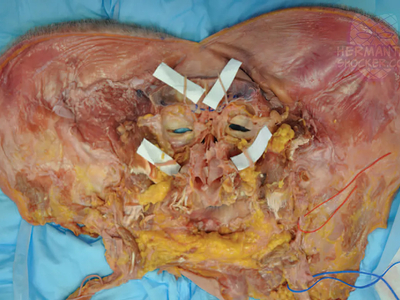

Composite facial allografts have become increasingly popular in the reconstruction of complex facial defects. Good to excellent aesthetic results can be achieved, particularly when a foundation of donor skeleton has been transferred...